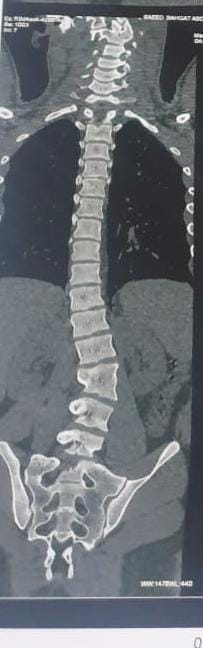

نجح فريق طبى بقسم جراحة المخ والأعصاب بمستشفى تمى الأمديد بالدقهلية فى إجراء اول جراحة دقيقة لإصلاح اعوجاج بالعمود الفقرى لشاب يبلغ من العمر 21 عاماً .

وأضاف مدكور أنه جرى استقبال المريض وهو يعانى من الالام شديدة بالظهر مع عدم الاستجابه للعلاج الدوائي والعلاج الطبيعى وعقب الفحص تبين وجود اعوجاج بالفقرات الصدريه والقطنيه بالعمود الفقري.

فيما أوضح الدكتور احمد البيلى وكيل المديرية للطب العلاجى أنه عقب مناظرة الاشعة والفحوصات تم إجراء العملية التى استغرقت 4 ساعات كاملة لإصلاح الاعوجاج بواسطه تثبيت الفقرات الصدريه والقطنيه واستعدال العمود الفقرى مع خروج المريض من المستشفى وتحسن حالته